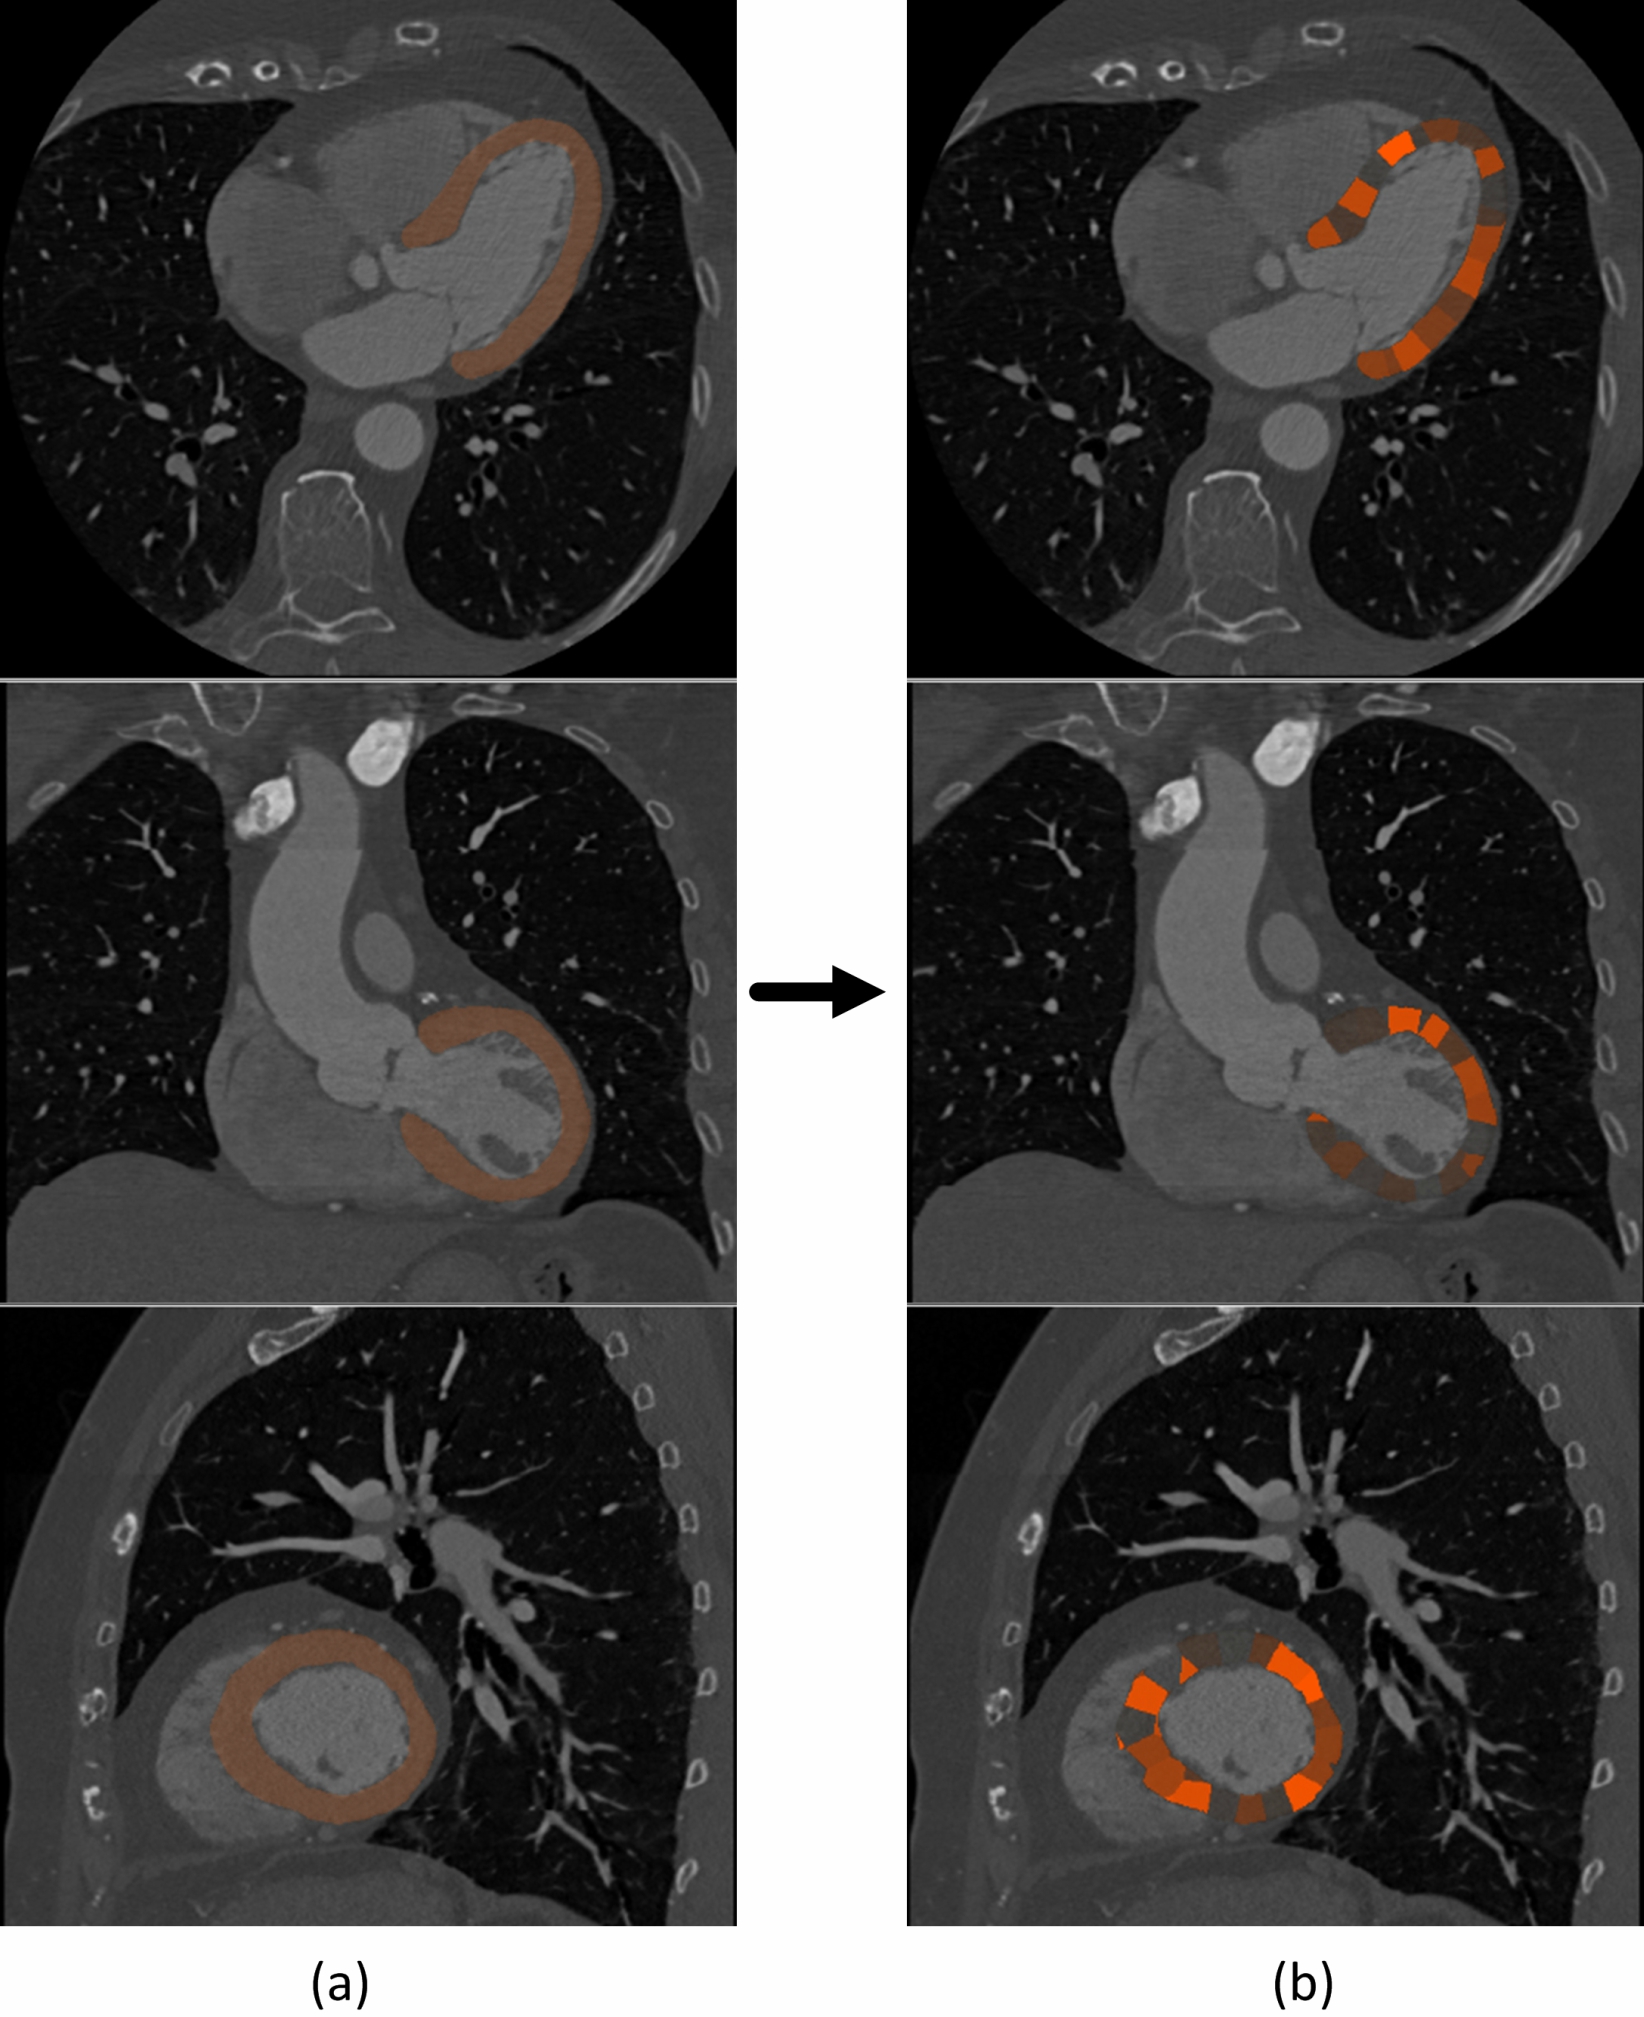

The segmentation is performed in two stages. First, the LV myocardium is localized, and second, the voxels in the region of interest are classified. In our preliminary work [Zreik et al., 2016], the LV myocardium was localized using a bounding box [de Vos et al., 2017] created by an independent CNN. In this work, localization and voxel classification are both performed using the same CNN, circumventing the need for an independent localization method. Therefore, to localize the LV myocardium, equidistantly spaced voxels in the whole image are classified as LV myocardium or as background. By applying 3D Gaussian smoothing to the obtained sparse classification result followed by thresholding of the smoothed probabilities, a rough segmentation of the LV myocardium is obtained. Thereafter, to precisely segment the myocardium, only the voxels on the surface of the rough segmentation are iteratively classified as LV myocardium or as background. Note that reclassification of the voxels inside the rough segmentation is not needed as the myocardium is a compact structure. The iterative voxel classifications is repeated until all surface voxels are classified as LV myocardium. Fig. 4 illustrates the segmentation process.

Since a functionally significant stenosis is expected to have a local impact on the myocardial blood perfusion [Mehra et al., 2011, Rossi et al., 2014], the LV myocardium is divided into 500 spatially connected clusters. Clustering is achieved using the fast K-means algorithm [Sculley, 2010], based on the spatial location of the myocardial voxels. A typical example of such a clustering is shown in Fig. 7.

Fig. 8 illustrates segmentation results. Quantitative evaluation of the segmentation performed on the 20 test scans resulted in a Dice coefficient of and a MAD of mm. Qualitative evaluation of the segmentation was performed in all 146 test scans. Results are summarized in Table 2.